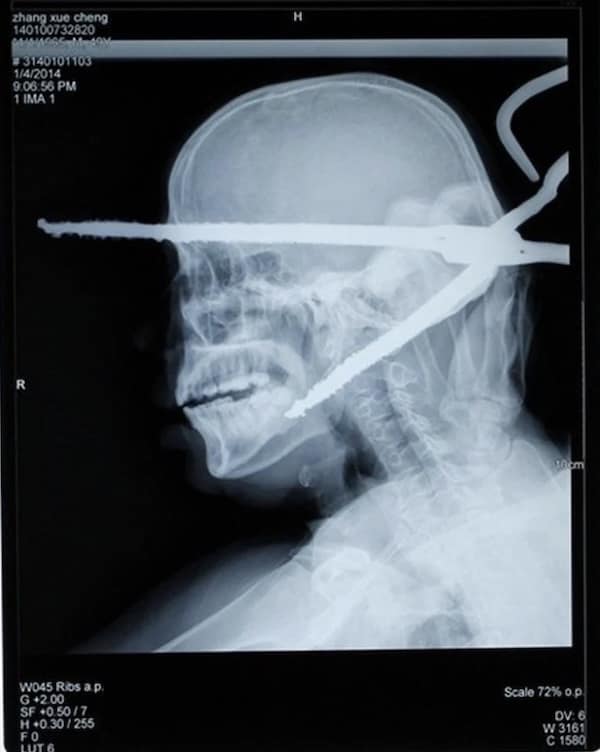

Weird xray photos

I used to think that nothing could surprise me anymore—until I stumbled upon some weird x-ray photos that made me reconsider my stance on human ingenuity (or lack thereof). Apparently, some people have a knack for getting objects lodged where they absolutely shouldn’t be. If you’ve ever wondered how not to use everyday items, these images might provide some unintended guidance.

This collection showcases 31 bizarre x-ray images that defy logic and anatomy textbooks alike. Each photo reveals unexpected objects making cameo appearances inside the human body, turning medical imaging into a gallery of the absurd. From common household items inexplicably found in unusual places to anomalies that would leave even seasoned doctors scratching their heads, these images offer a perplexing glimpse into the more “creative” side of medical emergencies. They highlight the intersection of curiosity, misadventure, and perhaps a dash of poor decision-making, all captured through the lens of radiology.